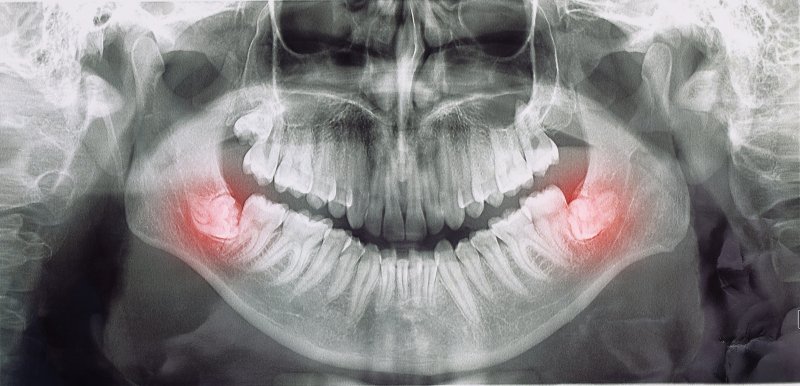

Wisdom teeth remain a mystery for many patients, especially those who need to have them removed. It’s often heard that they no longer serve a purpose, but why? What changed to make these third molars unnecessary? You can find out by reading the following article and learning how to tell when it might be time to say goodbye to these extra teeth.